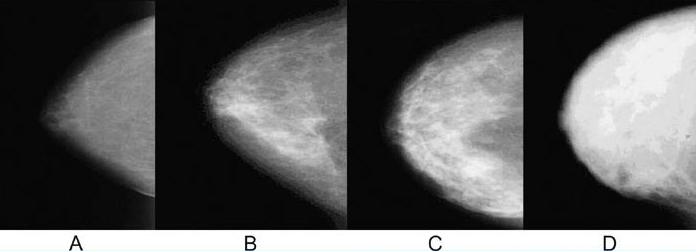

유방촬영술 상에서 지방조직은 어두운 음영으로 나타나게 되고 유선조직은 하얗게 나타나는데 위 사진에서 보면 왼쪽 A는 하얗게 보이는 유선조직의 분포가 적으며 대체적으로 어두운 음영인 지방조직의 분포가 많은 지방화유방이며 D로 갈수록 유선조직이 풍부해 지며 하얗게 보이는 부분이 넓게 퍼져있는 즉, 유선조직이 조밀하게 뭉쳐있는 분포인 치밀유방이라고 합니다.

동양인들은 서양인들에 비해 유방이 작고 유선조직이 풍부하게 발달되어 치밀유방인 경우가 많은데 이런 경우에는 유선조직에 병변들이 가려 발견이 어려운 경우가 많으므로 유방초음파 검사를 받아보시는 것이 좋습니다.